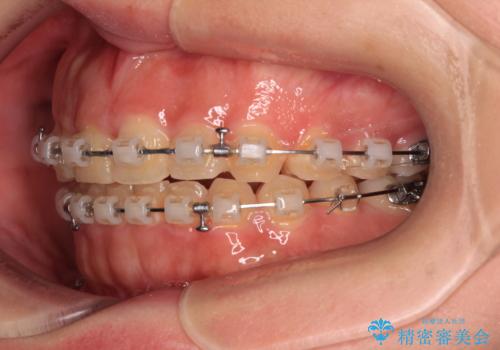

- クリアブラケット

口元の突出感は強くなかったため非抜歯矯正での対応となりますが、捻転を改善する際に上顎前歯が前突する可能性があったため、上顎臼歯部にアンカースクリューを使用して、歯列が前方に転位しないようにすることとしました。

また舌のトレーニングを行うことで、上顎前歯の突出予防や上下前歯に隙間ができなくなるようにしました。

ワイヤー矯正でもインビザラインでも対応可能でしたが、上顎歯列が前方位であるときには、ワイヤー矯正の方がより良い仕上がりとなる可能性が高いため、ワイヤー矯正をおすすめいたしました。